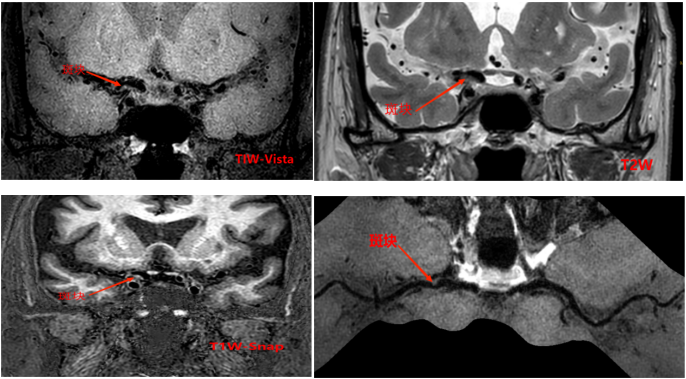

4招丨发现血管炎性病变

c942acd936317f3ed8349105fac4e327.png

左图T1W平扫见大脑中动脉M2段管壁增厚明显并呈等高信号,右图T1W增强后见管壁强化明显,提示该处有活动性炎症。

91afb25b92d13a6bf5254e21724c0d78.png

3D曲面重建后更直观明确血管壁炎症的位置和情况。